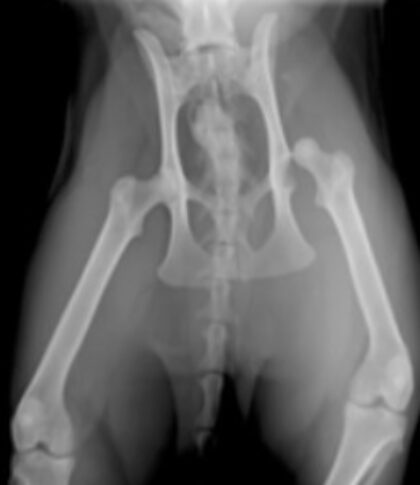

Dieses vetinar gibt einen vertiefenden Einblick in die Orthopädie und Traumatologie beim Kleintier und es wird auf orthopädische Notfälle gezielt eingegangen. Was ist ein orthopädischer Notfall bzw. wie lange kann dieser mit der weiteren Behandlung warten? Besprochen werden offene Frakturen und Luxationen. Diese werden im Notfall häufig vorgestellt, aber stellen eigentlich keine Notfälle dar. Der Patient kann zwar durch das Trauma in einem lebensbedrohlichen Zustand sein, aber die orthopädische Erkrankung ist kein wirklicher Notfall und kann behandelt werden, wenn das Tier stabil ist. Das Timing dieser weiteren Behandlung, die dann selbst oder vom Spezialisten durchgeführt werden kann, als auch die Versorgung bis dorthin soll erklärt und ein Leitfaden dargestellt werden.

Ziel dieses vetinars ist es, eine korrekte Erstversorgung von orthopädische Verletzungen durchzuführen und einschätzen zu können, wann eine endgültige Versorgung indiziert ist. Zudem sollen kurz die möglichen Behandlungen erläutert werden.